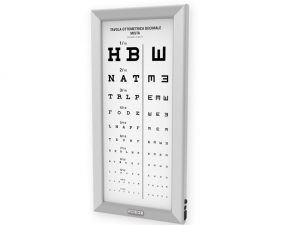

Tavole optometriche, Tavole optometriche a LED ultrapiatte

Tavole optometriche, Tavole optometriche a LED ultrapiatte

OTTOTIPO ULTRAPIATTO A LED – Pediatrico

455,00 € (555,10 € IVA incl.) -